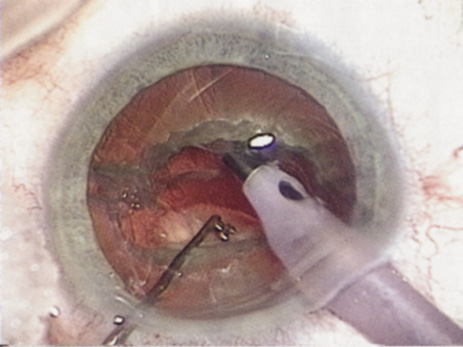

BRUNESCENT CATARACT

POSTERIOR POLAR CATARACTS